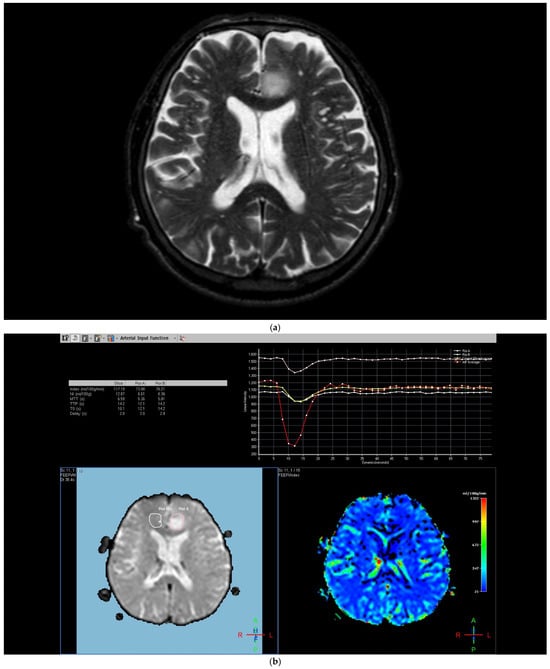

The region of interest (ROI) size ranged from 2 to 10 square millimeters in area, depending on the size of the tumor. rCBV values were obtained by identifying regions of maximal perfusion from color maps (Figure 1). While measuring the rCBV values, care was taken to avoid any vascular structures, cerebrospinal fluid, or areas with high susceptibility. For the appropriate placement of the ROI, the rCBV maps were coregistered with FLAIR/T2-weighted, post-contrast T1-weighted, or SWI/GRE images. For multiple metastatic lesions, the measurements were performed from the largest and most enhanced tumoral lesion.

Figure 1.

Brain magnetic resonance imaging (MRI) of a 52-year-old male with a low-grade glial tumor revealed (a) increased signal on a T2-weighted image, (b) hypoperfusion with a rCBV of 1.08 in perfusion-weighted imaging, Pink ROI is from tumor and white ROI is from contralateral parenchyma. and (c) a total of four ROIs—one from the peritumoral region (in blue), one from the contrast-enhancing tumoral area (in pink), and two from the contralateral tumor-free white matter areas corresponding to these regions (in white and red) in perfusion-weighted imaging.

The rCBV values within the tumor and the surrounding area of edema were calculated using the following equation: rCBV = CBV tumoral or peritumoral edema/CBV of the corresponding locations at the uninvolved contralateral brain parenchyma. Perfusion curves were obtained for each lesion. All measurements were performed by the same neuroradiologist (AEP) blinded to the histological diagnosis of the tumors.